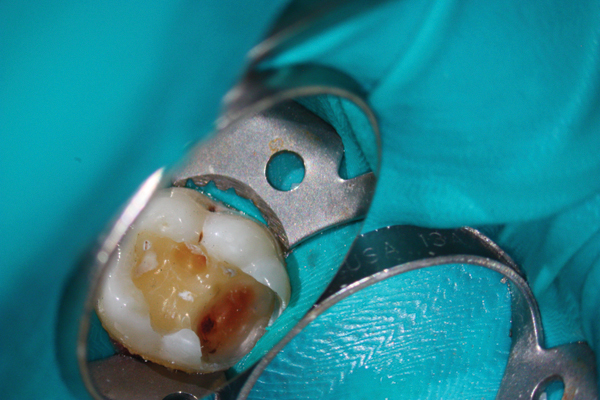

Fig 7. Preoperative pulp exposure after caries removal. Courtesy of Dr. Mohammed A. Alharbi.

Figure 7

Fig 8. Direct pulp coverage with BC Putty. Courtesy of Dr. Mohammed A. Alharbi.

Figure 8

Figure 6 shows the preoperative radiograph of an apparent carious exposure on tooth No. 19 of a 20-year-old male patient. A diagnosis of reversible pulpitis was made based on the history and clinical exam. After anesthesia and caries removal, the exposure was seen (Figure 7) and covered with BC RRM-Fast Set (Figure 8). After the BC base had fully set, a bonded resin was placed and a postoperative radiograph taken (Figure 9). At the 6-month follow-up visit, the tooth was asymptomatic and tested vital. Radiographically, no signs of pathology were noted (Figure 10).